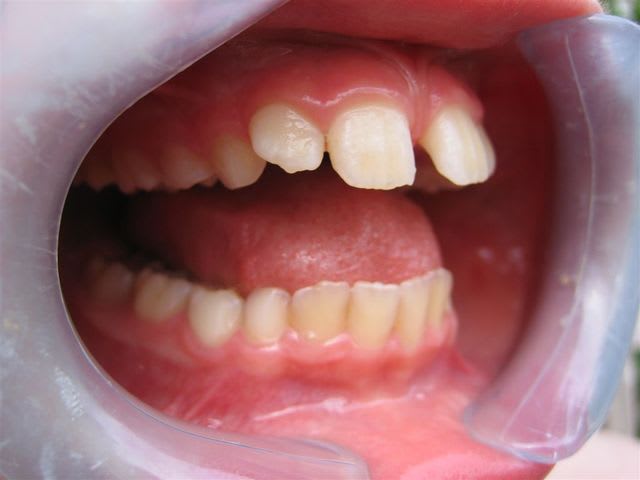

... ma gamine, bientôt 9 ans.

Père CD ... traitement d'ortho.

Mère CD ... traitement d'ortho.

Les conseils sont les bienvenus.

pour ta gamine je ne suis pas spécialiste mais il me semble que la première chose à faire est une freinectomie,suivie d'un apparei pour corriger l'occlusion

C’est un cas simple ou il faut juste stimuler un peu la croissance et reformer les arcades.

C’est le type même du traitement d’interception en denture mixte.

... freinectomie; elle se fait de moins en moins actuellement d'après l'ortho; et heureusement, je n'avais pas tellement envie de m'y coller!

... elle est en classe I, avec une grosse supra.

TT "fonctionnel" prévu dans qqs semaines.

... c'est en cours ... un appareil de chez Rocky Mountain va être mis en place, à porter environ 16 heures/jour; il va falloir que je m'en fasse expliquer le principe lors de la séance de pose.